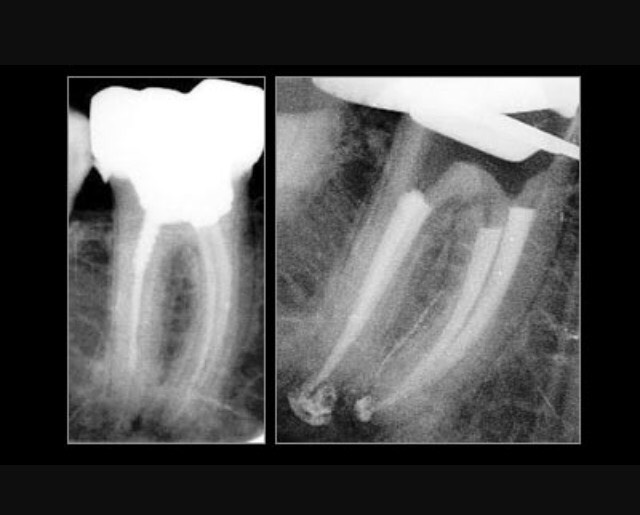

Lorsqu'un traitement endodontique initial apparaît inadéquat ou a échoué, il convient de retraiter une dent en éliminant tout matériau d'obturation canalaire et en procédant de nouveau au nettoyage, à la mise en forme et à l'obturation des canaux. Sur une dent couronnée, la prothèse doit être déposée.

Ce nouveau traitement est indiqué après un examen clinique rigoureux qui élimine les causes d'échec non endodontiques.